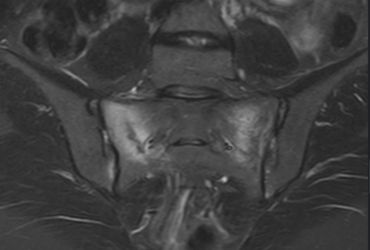

Whilst severe pelvic fractures are treated by orthopaedic surgeons in trauma centres, spontaneous sacral insufficiency fractures might be treated by endocrinologists, or rehabilitation physicians. But here are my comments!